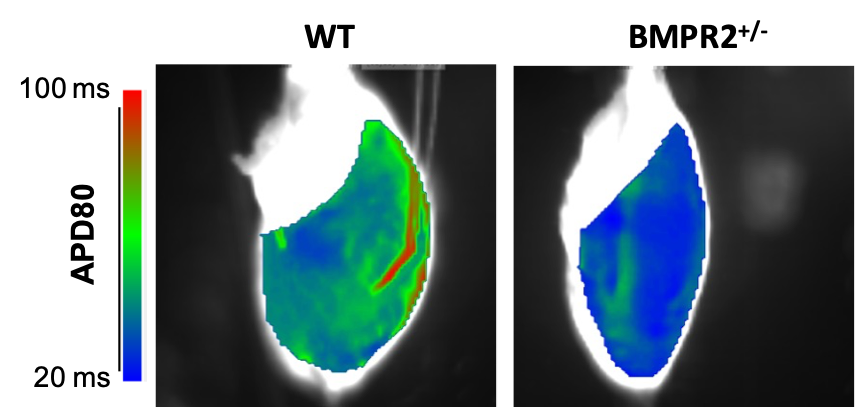

- Etude des altérations cardiaques droites chez les animaux transgéniques adultes avec une mutation BMPR2 (Bone Morphogenetic Protein Receptor 2) (collaboration avec l’équipe 3 de l’unité)en conditions physiologiques (normoxiques – Figure 1) ou pathologiques (HTP induite par une hypoxie chronique).